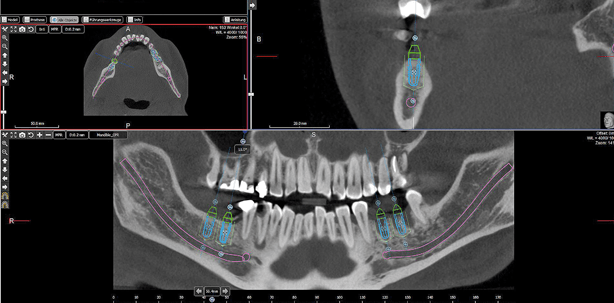

Mit dem integrierten Implantatplanungsmodul der WFI4 (Abb. 3a) werden die Implantate virtuell geplant. Alle gängigen Implantatsysteme sind integriert. Die zugehörigen Bohrhülsen, die Dimension der Laboranaloge sowie Abutmentgeometrien und Anchorpins sind – soweit der Hersteller die Angaben freigegeben hat – ebenfalls integriert. Es ist jederzeit möglich, Hülsen, Supports und Extrusionen frei zu definieren und als Vorlage abzuspeichern. Nach Planung der Implantate erfolgt die Erstellung eines umfangreichen Reports. Dieser dient während der OP als Bohr- und Insertionsprotokoll. Alle Angaben wie Implantathersteller, Implantatgeometrie, Position und Knochendichte sind auf dem Protokoll vermerkt.

3-D-Überlagerung des STL-Gipsmodells

Über den in WFI4 integrierten STL-Import und Registrierungsassistenten wird das STL-Gipsmodell in den DICOM-Diagnosedatensatz des Patienten importiert. Die grobe Ausrichtung des Modells erfolgt durch Festlegung von mindestens drei Punkten (Abb. 4a). Nach Vorregistrierung erfolgt die automatische 3-D-Anpassung. Hierbei berechnet die Software sekundenschnell die optimale Überlagerung und fügt das STL-Modell absolut deckungsgleich in den Diagnosedatensatz ein (Abb. 4b).